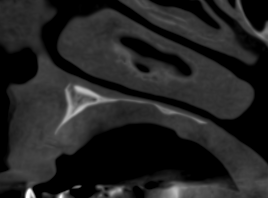

Cuando un paciente presenta reabsorción ósea avanzada o defectos estructurales, las radiografías 2D ofrecen una perspectiva incompleta. El CBCT es la única herramienta que permite al implantólogo conocer la morfología real del hueso en tres dimensiones, minimizando los riesgos quirúrgicos.

La capacidad del CBCT para mostrar la anatomía tridimensional es la base de un tratamiento seguro. Con esta tecnología es posible:

- Visualización de Estructuras Críticas: Permite mapear con seguridad estructuras vitales como el nervio alveolar inferior o el suelo del seno maxilar, evitando lesiones.

- Detección de Defectos: Identificación de irregularidades, dehiscencias o defectos óseos que deben ser abordados antes o durante la colocación del implante.